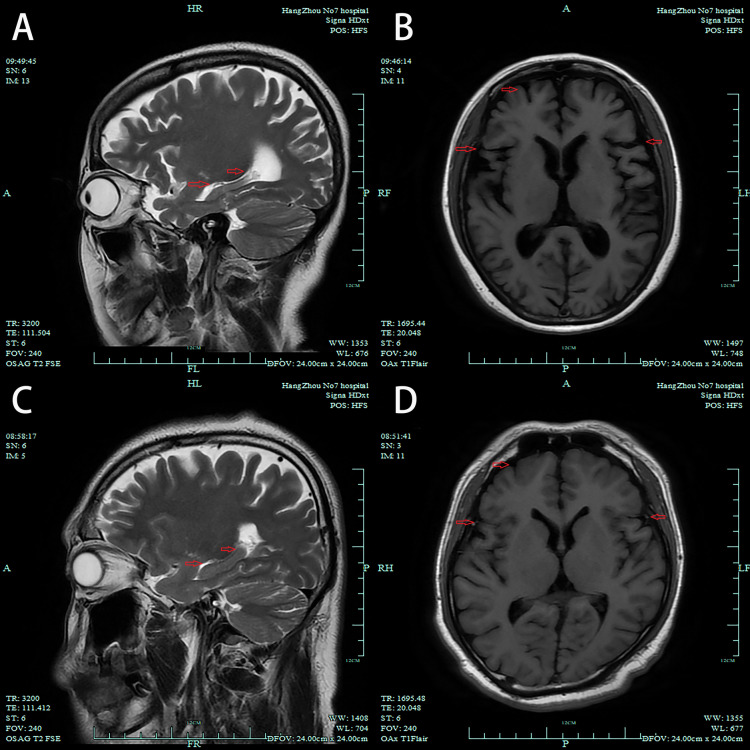

家族性阿尔茨海默病(FAD)通常与早老素1 (PSEN1)突变有关,其特点是常染色体显性遗传,与散发性阿尔茨海默病相比发病更早。我们报告了一位48岁的女性患者,她被诊断为早发性FAD,携带PSEN1 (p.Met139Leu)突变,最初表现为认知能力下降,后来发展为急性精神病症状。尽管联合抗精神病和抗痴呆治疗,她的认知功能迅速恶化,导致严重的功能丧失。本病例突出了FAD的非典型早期精神表现,强调了对出现认知和精神症状的年轻患者进行基因检测和及时干预的重要性。

Familial Alzheimer's disease (FAD), often linked to presenilin 1 (PSEN1) mutations, is characterized by an autosomal dominant inheritance and earlier onset compared to sporadic Alzheimer's disease. We report a 48-year-old female patient diagnosed with early-onset FAD carrying a PSEN1 (p.Met139Leu) mutation, who initially presented with cognitive decline and later developed acute psychotic symptoms. Despite combined antipsychotic and anti-dementia treatment, her cognitive function rapidly deteriorated, resulting in significant functional loss. This case highlights the atypical early psychiatric manifestations of FAD, emphasizing the importance of genetic testing and prompt intervention in younger patients presenting with cognitive and psychiatric symptoms.